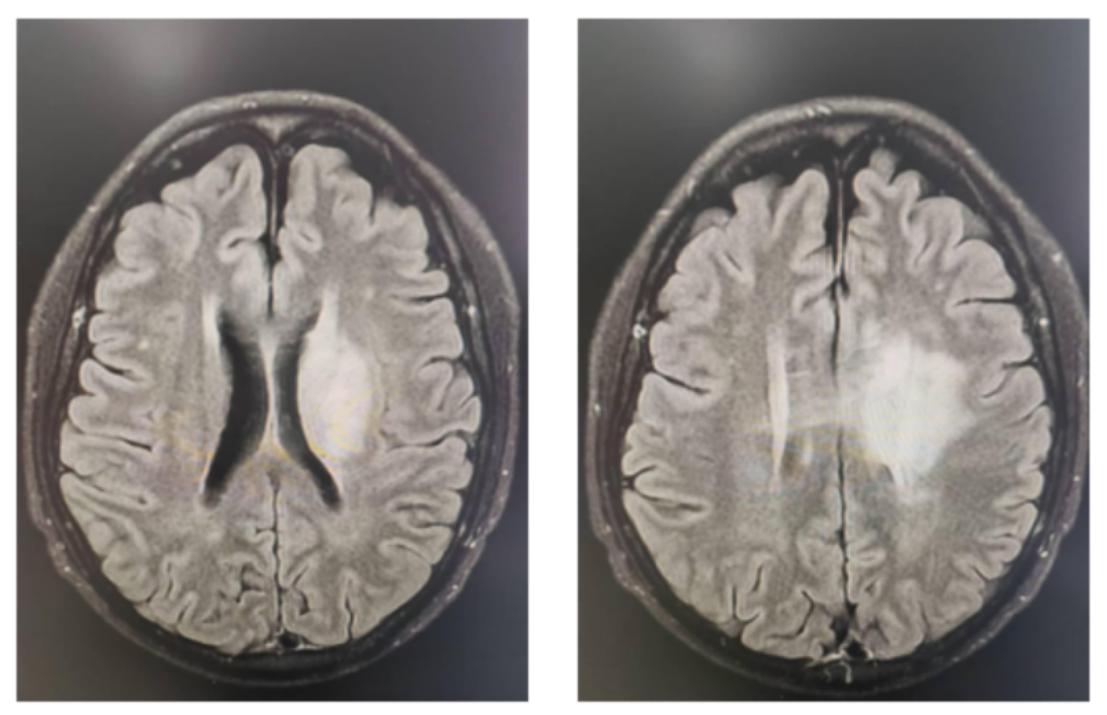

患者男性,61岁,主诉为“左眼视物模糊,左眼睑下垂和左眼球固定2月”,无头晕、头痛和肢体乏力等不适。2023-04-20在当地医院行MR检查,显示中脑、丘脑、基底节、放射冠、海马及颞叶深部多发异常信号,考虑肿瘤性病变,低级别胶质瘤可能(图1)。2023-04-25在我院行PET/MR检查,提示左侧脑室旁、左侧中脑、丘脑、颞叶海马区多发异常信号灶代谢略活跃,增强扫描中脑病灶明显不均匀强化,余病灶强化不明显,不除外恶性病变可能。2023-05-10在外院行立体定向中脑病变活检术,术后病理提示:病变组织符合DMG,免疫组化显示:IDH-1(散在弱+),Ki-67(约40%),MGMT(-),H3K27M(部分弱+,突变型)。最后诊断:DMG,H3K27M突变型,WHO 4级。

图1 初诊影像学